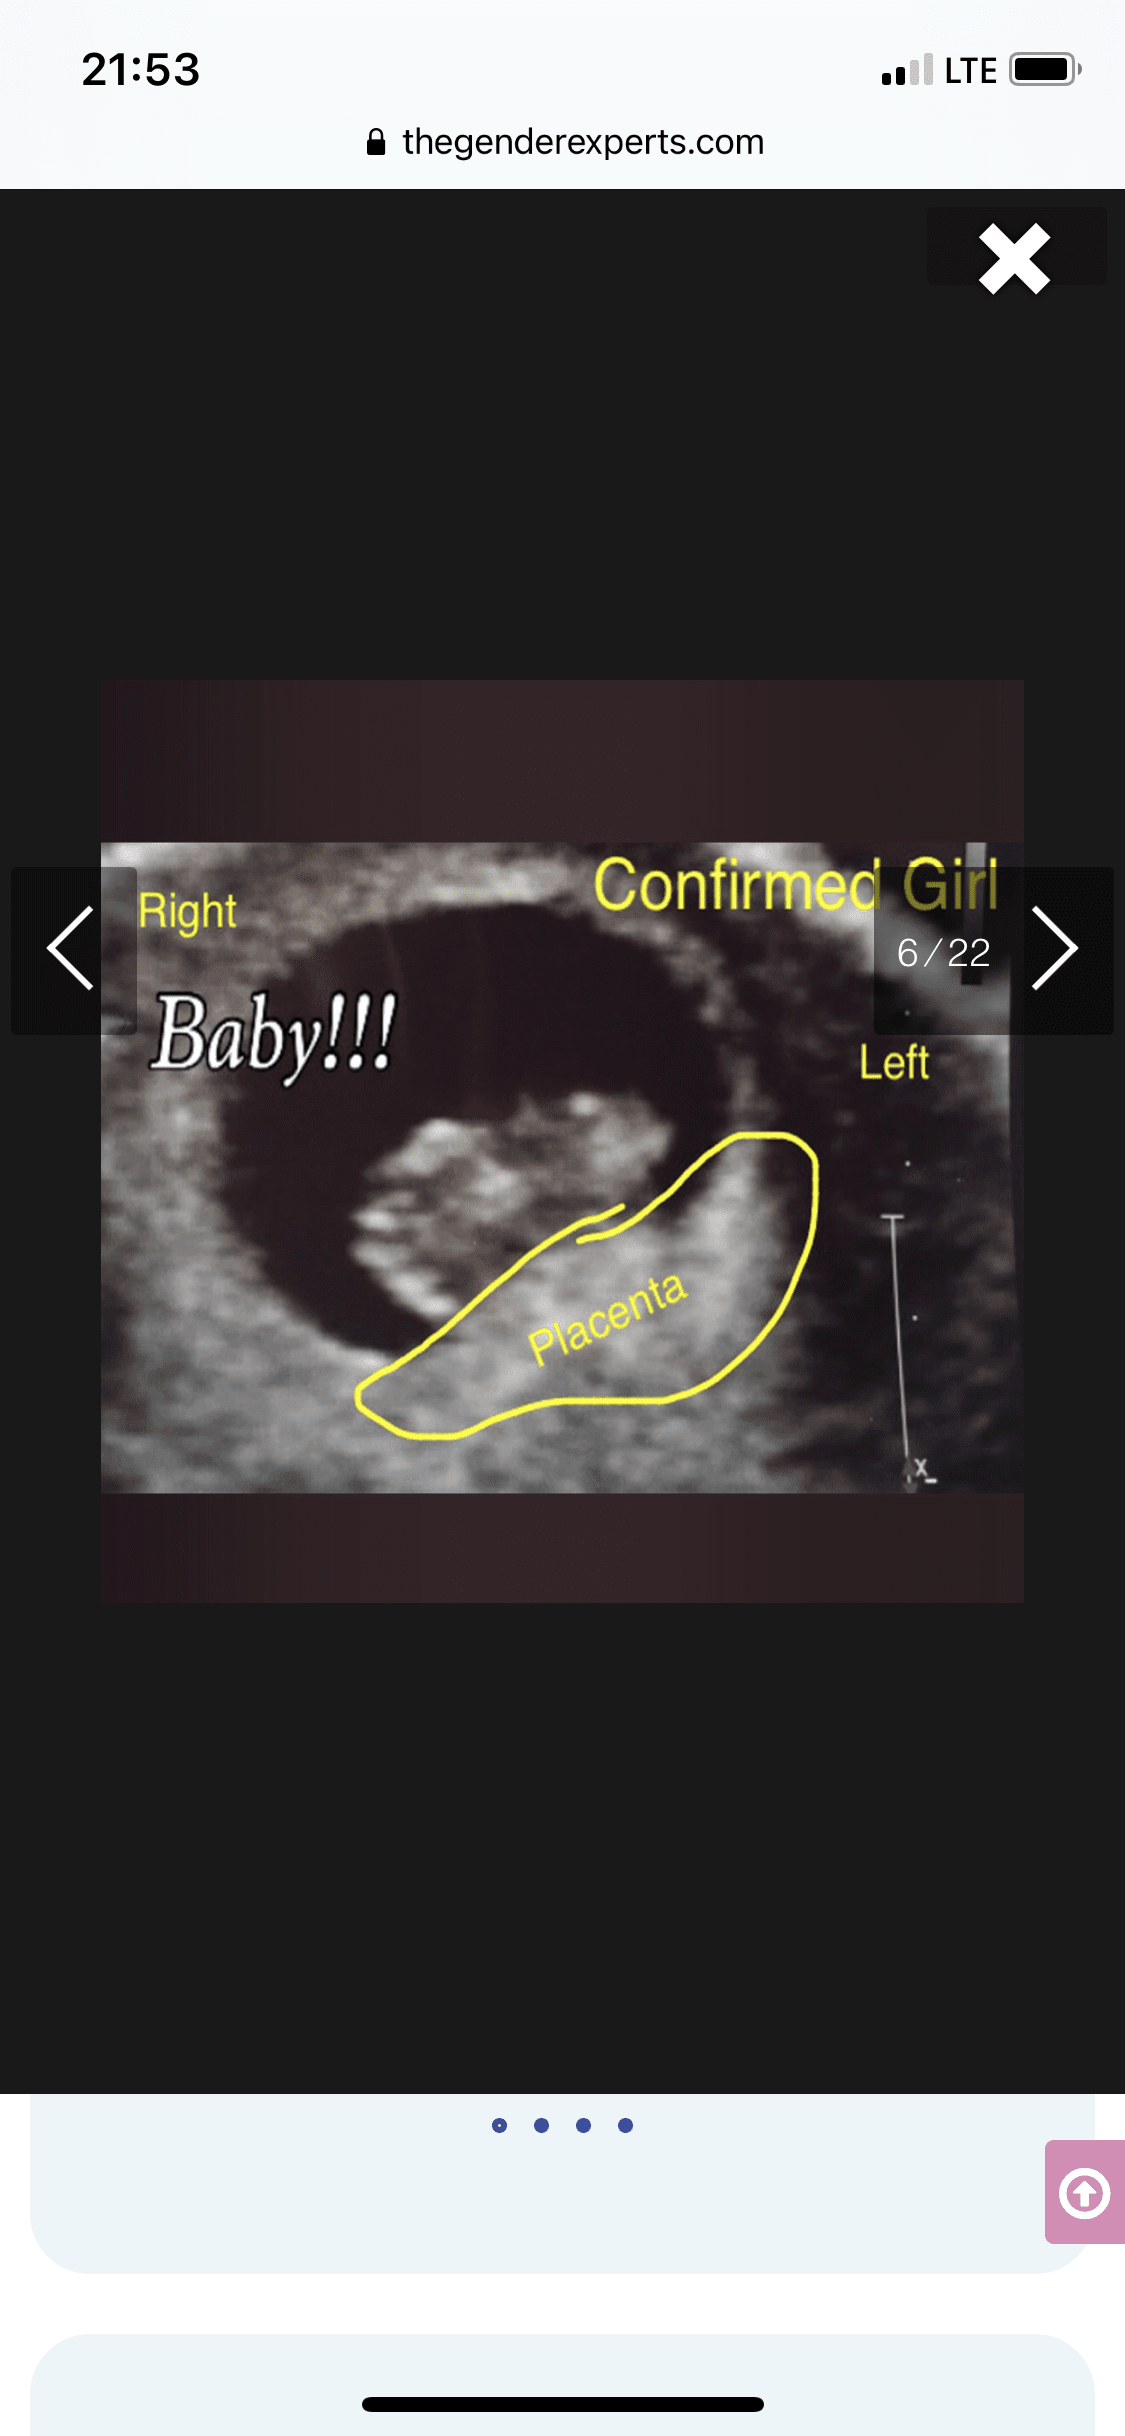

Tak dokładnie chodzi o położenie kosmowki z której potem wytworzy się łożysko. Metoda się sprawdza tak jak mówisz 50/50Aaa pytałam wtedy o położenie kosmowki.